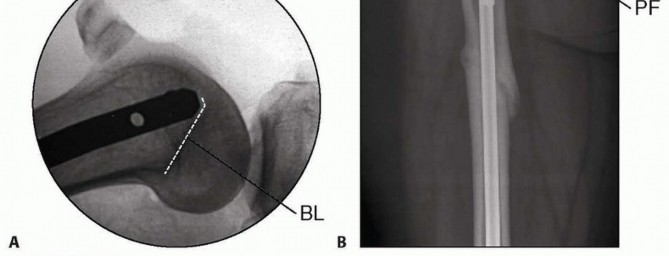

Once the fracture is reduced on the AP and lateral images, the surgeon passes the guidewire to end just below the level of the piriformis fossa. This is done to ensure that reaming is performed past the level of the lesser trochanter because the reamers stop at the beaded portion of the guidewire. 5. ## Reaming Reaming should begin with an end-cutting reamer (typically size 8 mm or 9 mm in diameter). Fracture reduction must be maintained throughout the reaming process to minimize eccentric reaming. Reaming should be performed slowly and in 0.5-mm increments to prevent thermal necrosis. The approximate nail diameter is selected based on the preoperative measurement of the femoral isthmus. The final nail diameter should be selected based on the size of the reamer that provides the initial cortical chatter. The canal is reamed to 1.0 to 1.5 mm over the selected nail diameter. Nail length can be determined multiple ways: A radiolucent ruler can be placed on the anterior aspect of the femur. The nail should end above the level of the lesser trochanter on the AP radiograph and should be measured so that it is deep to the apex of the line of Blumensaat on the lateral view (see FIG 1C).  --- TECH FIG 1 • Schematic diagram of a lateral view of the knee, obtaining femoral length measurement using the twoguidewire technique. The amount of guidewire B (asterisk) indicated by the bracket equals the amount of guidewire A in the femoral canal. Alternatively, a second guidewire of the same length can be inserted into the knee to end just deep to the apex of the line of Blumensaat on the lateral fluoroscopic image. This additional guidewire is clamped at the level of the guidewire already in place. The portion distal to the guidewire in place is measured to equal the amount of guidewire in the femoral canal ( TECH FIG 1). In addition, many nailing systems have system-specific measurement guides that are outlined in their technique manuals. If the measurement is between nail sizes, the shorter nail is selected. Length can be added with an end cap if required. 6. ## Placing the Nail Once the nail size is selected, the nail is inserted over the guidewire. Most current systems allow the beaded-tip guidewire to pass through the cannulated nail. If an older system is being used, then the beaded-tip guidewire must be exchanged for a smoothtip guidewire using an exchange tube. If guidewire exchange is required, the surgeon ensures correct placement of the smooth-tip guidewire on the AP and lateral images before nail insertion. The nail is inserted over the guidewire and should pass relatively easily. If the nail does not advance easily, the surgeon performs a careful AP and lateral fluoroscopic assessment of the fracture reduction and nail placement. Nail insertion depth is assessed on the lateral knee radiograph. The nail should end proximal to the apex of the line of Blumensaat to ensure subchondral placement ( TECH FIG 2A). The surgeon confirms that fracture length and alignment have been restored on the AP and lateral radiographs. The surgeon confirms that the nail length selected puts the proximal tip of the nail ending at or above the level of the lesser trochanter ( TECH FIG 2B). The nail is advanced if the proximal tip does not end at or above the level of the lesser trochanter. If this leaves the nail countersunk, end caps can be selected to gain nail length. Care must be taken to remain below the piriformis fossa to avoid proximal nail protrusion. The nail is locked distally using the distal interlocking guides. We typically use one lateral to medial distal interlocking screw for transverse midshaft femoral fractures, and a second anterolateral to posteromedial distal interlocking screw for comminuted or distal femoral fractures. Using live fluoroscopy, the fluoroscopic machine is rotated about the knee to assess the length of the interlocking

--- TECH FIG 1 • Schematic diagram of a lateral view of the knee, obtaining femoral length measurement using the twoguidewire technique. The amount of guidewire B (asterisk) indicated by the bracket equals the amount of guidewire A in the femoral canal. Alternatively, a second guidewire of the same length can be inserted into the knee to end just deep to the apex of the line of Blumensaat on the lateral fluoroscopic image. This additional guidewire is clamped at the level of the guidewire already in place. The portion distal to the guidewire in place is measured to equal the amount of guidewire in the femoral canal ( TECH FIG 1). In addition, many nailing systems have system-specific measurement guides that are outlined in their technique manuals. If the measurement is between nail sizes, the shorter nail is selected. Length can be added with an end cap if required. 6. ## Placing the Nail Once the nail size is selected, the nail is inserted over the guidewire. Most current systems allow the beaded-tip guidewire to pass through the cannulated nail. If an older system is being used, then the beaded-tip guidewire must be exchanged for a smoothtip guidewire using an exchange tube. If guidewire exchange is required, the surgeon ensures correct placement of the smooth-tip guidewire on the AP and lateral images before nail insertion. The nail is inserted over the guidewire and should pass relatively easily. If the nail does not advance easily, the surgeon performs a careful AP and lateral fluoroscopic assessment of the fracture reduction and nail placement. Nail insertion depth is assessed on the lateral knee radiograph. The nail should end proximal to the apex of the line of Blumensaat to ensure subchondral placement ( TECH FIG 2A). The surgeon confirms that fracture length and alignment have been restored on the AP and lateral radiographs. The surgeon confirms that the nail length selected puts the proximal tip of the nail ending at or above the level of the lesser trochanter ( TECH FIG 2B). The nail is advanced if the proximal tip does not end at or above the level of the lesser trochanter. If this leaves the nail countersunk, end caps can be selected to gain nail length. Care must be taken to remain below the piriformis fossa to avoid proximal nail protrusion. The nail is locked distally using the distal interlocking guides. We typically use one lateral to medial distal interlocking screw for transverse midshaft femoral fractures, and a second anterolateral to posteromedial distal interlocking screw for comminuted or distal femoral fractures. Using live fluoroscopy, the fluoroscopic machine is rotated about the knee to assess the length of the interlocking

---  TECH FIG 2 • A. Postoperative lateral radiograph of the knee, showing correct retrograde femoral nail insertion depth deep to the line of Blumensaat (BL). B. Postoperative AP radiograph of the hip, showing correct retrograde femoral nail insertion depth above the lesser trochanter of the femur but below the radiographic landmark for the piriformis fossa (PF). The surgeon should consider using washers, a medial locking nut, or a locking end cap (which locks the most distal interlocking screw to the nail) as options for osteoporotic bone. Once distal interlocking screw fixation is complete, the surgeon reassesses the fracture reduction fluoroscopically. If any shortening has occurred, length can be regained by manual traction or by backslapping the nail with the insertion guide nail removal attachment (the surgeon must exercise caution when using this technique in patients with osteoporotic bone). 7. ## Screw Fixation Proximal interlocking screw fixation is performed in the anterior to posterior plane using the freehand perfect circle technique. 7 First, a magnified AP image of the proximal femur is obtained. The fluoroscopy machine is rotated until the proximal interlocking hole is seen as a “perfect circle” (also discussed in Chap. 44, Antegrade Intramedullary Nailing of the Femur; Tech Fig 4, Distal interlocking screw placement). A 1-cm incision is made in the proximal aspect of the thigh, anteriorly centered over the proximal interlocking hole, as visualized on the AP radiograph. Careful blunt dissection exposes the anterior femur. The proximal femur's dense cortical bone makes it difficult to start a hole using a standard drill bit. The pointed soft tissue guides from large external fixation systems or a pointed drill bit can be used to prevent slipping off of the anterior cortex. The femoral artery lies 1 cm medial to the femur at the level of the lesser trochanter, so the surgeon must avoid slipping off the femur medially. Once the drill passes through the first cortex, it is removed from the drill bit to confirm radiographically that it will pass though the nail by the appearance of a perfect circle within the proximal interlocking hole. Small changes in the drill angle can be made to ensure correct passage through the interlocking hole. With a mallet, the drill bit can be gently tapped through the nail hole. The drill is then reattached to complete drilling through the posterior aspect of the proximal femur. Because of the proximity of the sciatic nerve, care should be taken to ensure that the drill is not advanced too far past the posterior cortex. Before removing the drill, the surgeon must reconfirm correct rotational alignment by flexing the hip and knee and assessing the hip's internal and external rotation profile. It is compared with the normal internal and external rotation of the contralateral uninjured hip that was examined preoperatively. Screw length measurement can be confirmed with a frog-leg lateral or a true lateral view with flexing of the hip to clear the contralateral leg.

TECH FIG 2 • A. Postoperative lateral radiograph of the knee, showing correct retrograde femoral nail insertion depth deep to the line of Blumensaat (BL). B. Postoperative AP radiograph of the hip, showing correct retrograde femoral nail insertion depth above the lesser trochanter of the femur but below the radiographic landmark for the piriformis fossa (PF). The surgeon should consider using washers, a medial locking nut, or a locking end cap (which locks the most distal interlocking screw to the nail) as options for osteoporotic bone. Once distal interlocking screw fixation is complete, the surgeon reassesses the fracture reduction fluoroscopically. If any shortening has occurred, length can be regained by manual traction or by backslapping the nail with the insertion guide nail removal attachment (the surgeon must exercise caution when using this technique in patients with osteoporotic bone). 7. ## Screw Fixation Proximal interlocking screw fixation is performed in the anterior to posterior plane using the freehand perfect circle technique. 7 First, a magnified AP image of the proximal femur is obtained. The fluoroscopy machine is rotated until the proximal interlocking hole is seen as a “perfect circle” (also discussed in Chap. 44, Antegrade Intramedullary Nailing of the Femur; Tech Fig 4, Distal interlocking screw placement). A 1-cm incision is made in the proximal aspect of the thigh, anteriorly centered over the proximal interlocking hole, as visualized on the AP radiograph. Careful blunt dissection exposes the anterior femur. The proximal femur's dense cortical bone makes it difficult to start a hole using a standard drill bit. The pointed soft tissue guides from large external fixation systems or a pointed drill bit can be used to prevent slipping off of the anterior cortex. The femoral artery lies 1 cm medial to the femur at the level of the lesser trochanter, so the surgeon must avoid slipping off the femur medially. Once the drill passes through the first cortex, it is removed from the drill bit to confirm radiographically that it will pass though the nail by the appearance of a perfect circle within the proximal interlocking hole. Small changes in the drill angle can be made to ensure correct passage through the interlocking hole. With a mallet, the drill bit can be gently tapped through the nail hole. The drill is then reattached to complete drilling through the posterior aspect of the proximal femur. Because of the proximity of the sciatic nerve, care should be taken to ensure that the drill is not advanced too far past the posterior cortex. Before removing the drill, the surgeon must reconfirm correct rotational alignment by flexing the hip and knee and assessing the hip's internal and external rotation profile. It is compared with the normal internal and external rotation of the contralateral uninjured hip that was examined preoperatively. Screw length measurement can be confirmed with a frog-leg lateral or a true lateral view with flexing of the hip to clear the contralateral leg.